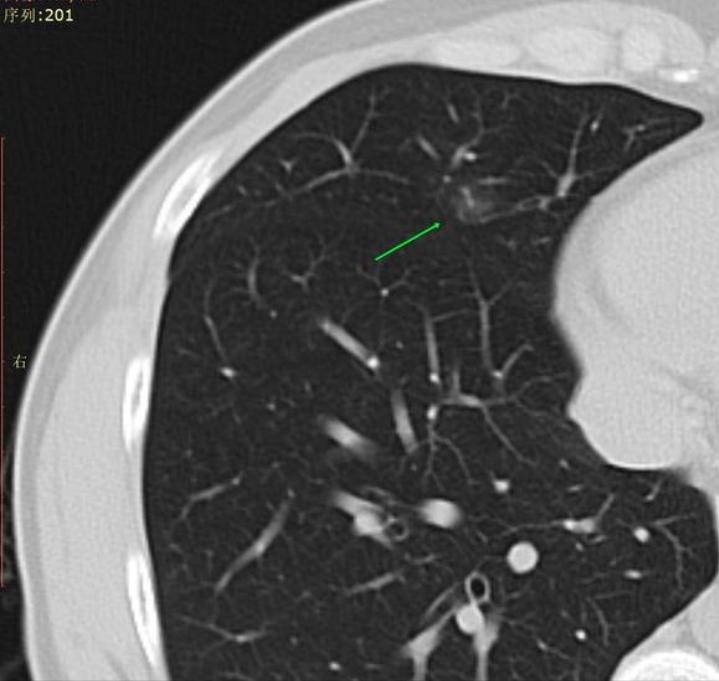

这是刚查出的结节。

在夭夭姐的教导下,我开始尝试发帖,很幸运连续发了三个帖子都得到了主任的回复(说声抱歉,因为着急帖子不太规范)。主任叫我拿2020年12月29日的CT影像对照,看看是不是漏诊了。我立刻重新发帖,贴上2020年的老片对照,主任回复我:“是炎症,口服拜复乐9天,夏枯草口服液1个月,会消。”我决定放下心里的焦虑,信任主任,安心消炎等待复查。